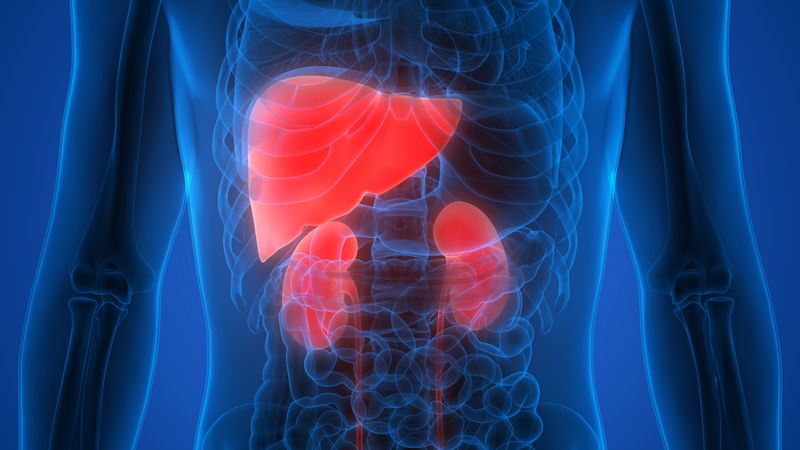

Image: Nadja Reissland, Durham University